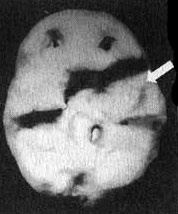

Вместе с Эндрю я отправился в отделение сканирования и, пока проводилось исследование, держал его за руку. Эндрю усадили в кресло, в вену ввели иглу, а через нее — малую дозу радиоизотопов. В это время Эндрю играл на ноутбуке в игру на концентрацию внимания. Через несколько минут иглу вынули, и он пошел в соседний кабинет, где делались снимки. Там его уложили на спину на специальный стол. В течение пятнадцати минут камера, медленно двигавшаяся по окружности вокруг головы Эндрю, производила съемку его мозга. Когда изображение было выведено на экран монитора, я подумал, что в ходе исследования была допущена какая-то ошибка. У Эндрю отсутствовала левая височная доля. Просмотрев все снимки, я убедился, что качество сканирования — хорошее. У него на самом деле не было левой височной доли. Что у него было? Киста? Опухоль? Инсульт? Рассматривая эти снимки на мониторе, я испытывал за него сильный страх. В то же время я чувствовал облегчение от того, что мы установили причину его агрессивности. В своих исследованиях и я, и мои коллеги установили связь между нарушениями в левой височной доле и агрессивностью. На следующий день на магнитно-резонансной томографии мы обнаружили у Эндрю на том месте, где обычно находится левая височная доля, кисту (мешок, заполненный жидкостью), размером с мячик для гольфа. Я знал, что эту кисту надо убрать. Однако поиск специалиста, который серьезно отнесся бы к нашим выводам, оказался трудным.

Отсутствие активности в левой височной доле у Эндрю

Трехмерное изображение нижней поверхности мозга

Иллюстрация к книге — Измените свой мозг - изменится и жизнь! [i_003.jpg]

Мозг Эндрю — левой височной доли не видно